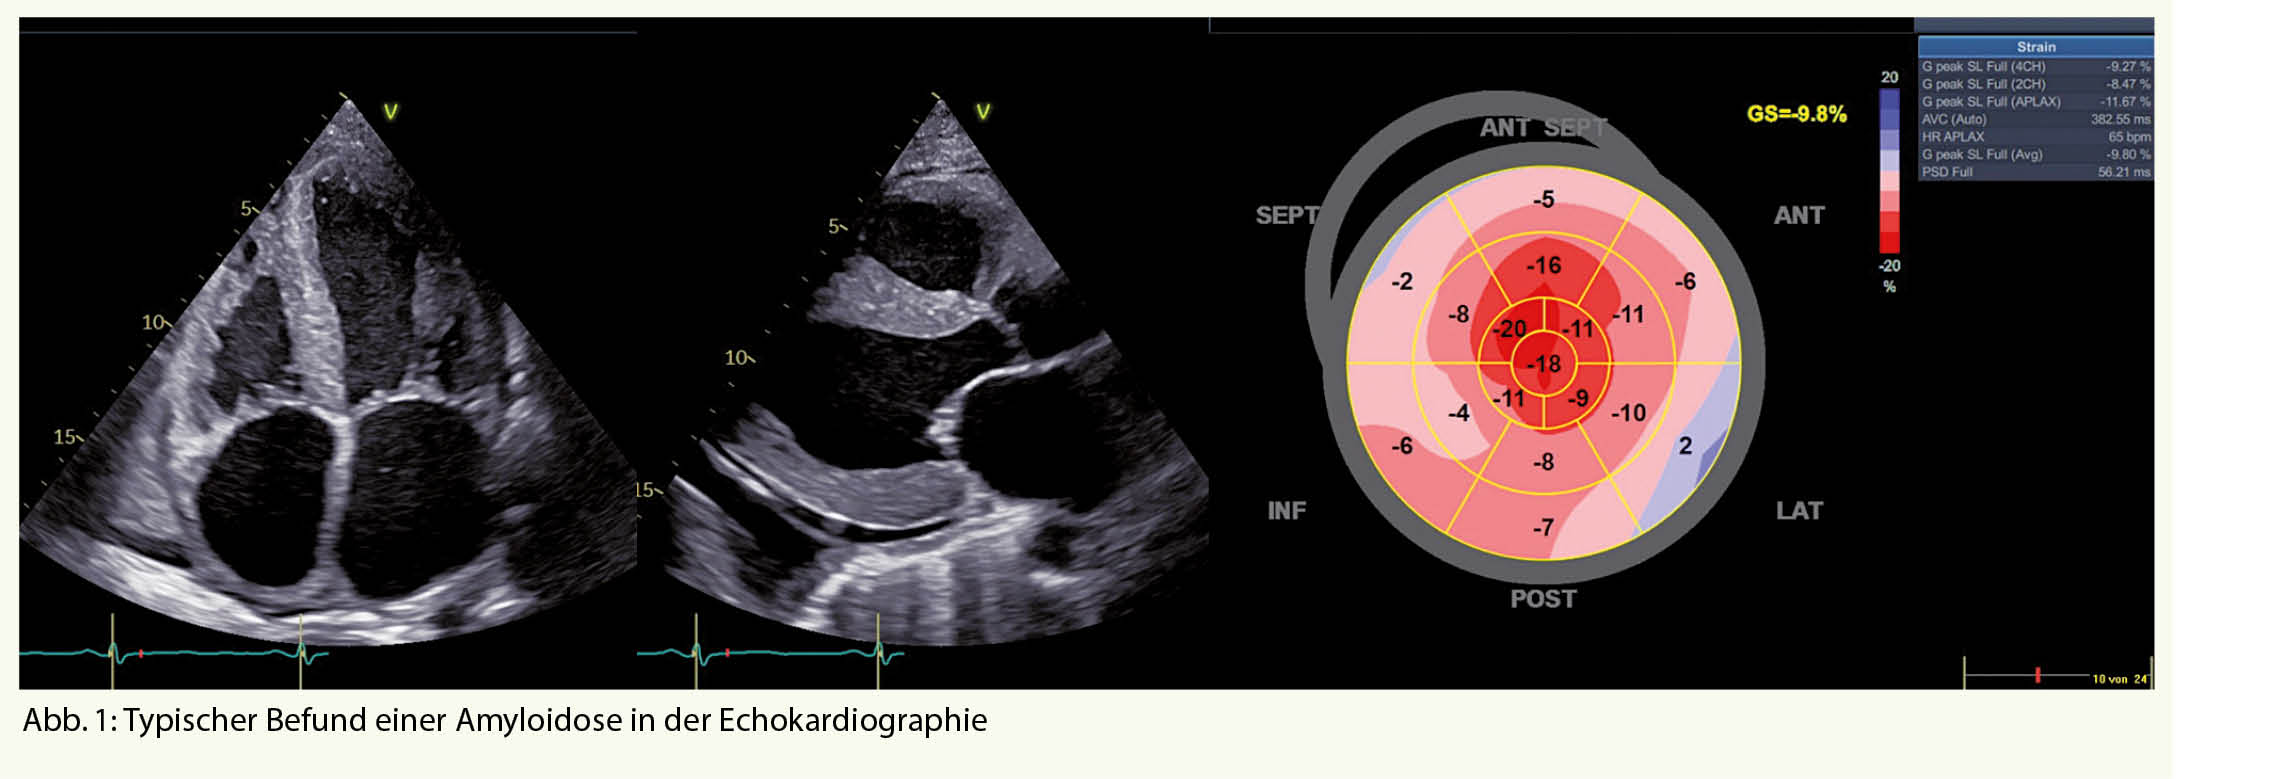

An eine kardiale Amyloidose sollte immer dann gedacht werden, wenn sich ein Patient mit Symptomen einer Herzinsuffizienz präsentiert und einen Echokardiographie- oder MRI-Befund aufweist der typisch für eine Amyloidose ist (Abb. 1 und Tab. 1) (1).